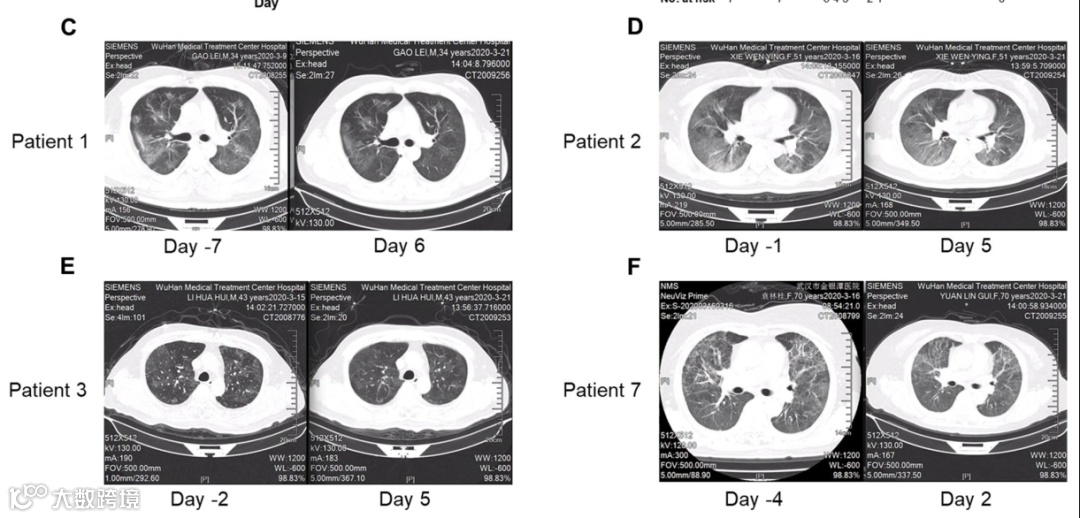

COVID-19 患者吸入haMSC-Exos前后胸部 CT 扫描的变化